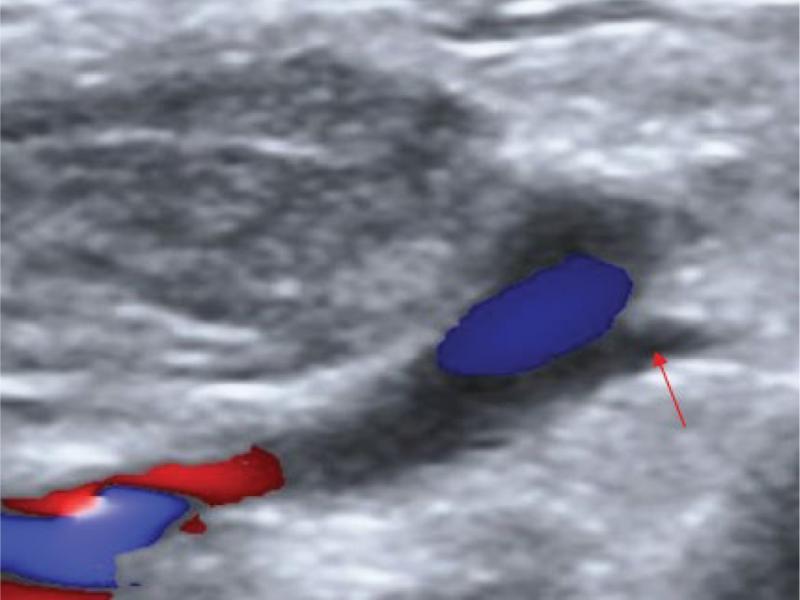

Fig. 2.

Ultrasonography of the jugulo-subclavian angle. Thoracic duct (red arrow)